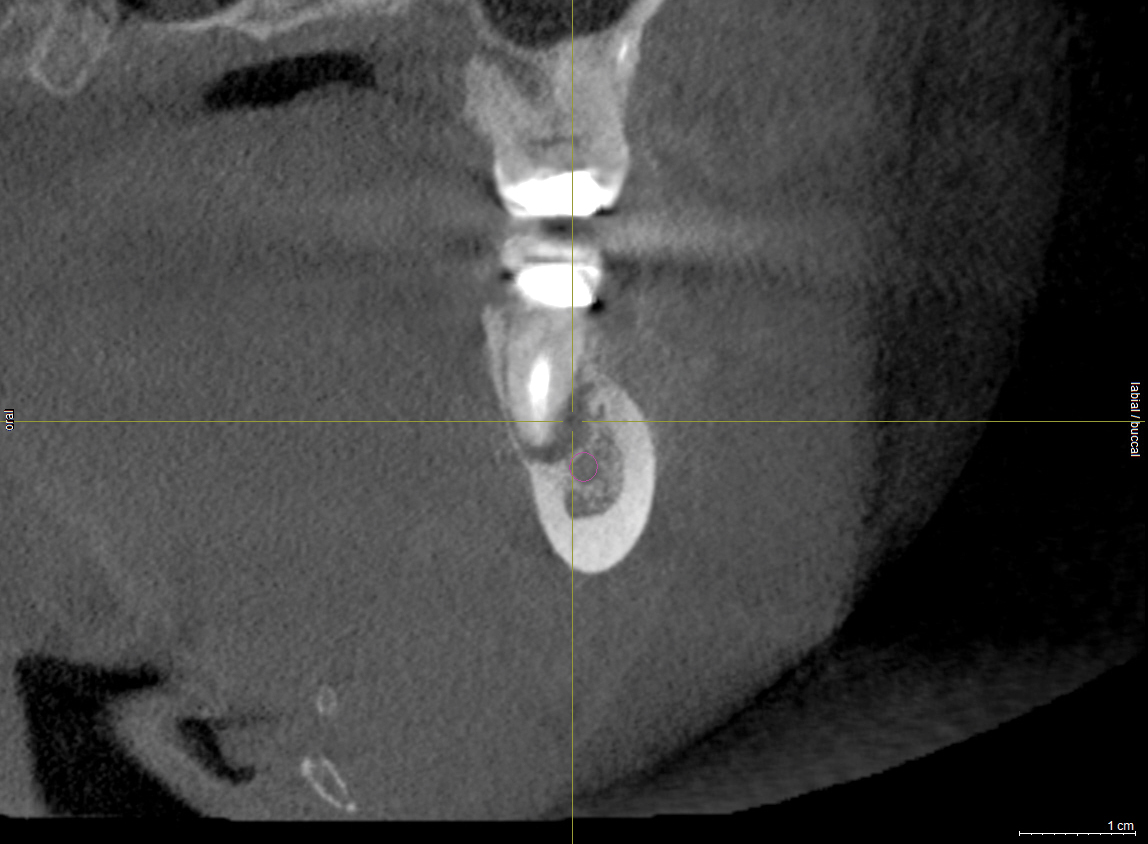

Fig 2. The implant restoration was completed 10 years ago and the patient has been able to accommodate the altered nerve sensation. Recently, the patient presented at one of the authors’ offices and a CBCT scan was ordered. It demonstrated that the implant at site No. 30 is closer to the inferior alveolar canal than previously envisioned and may be causing compression on the nerve.

Figure 2